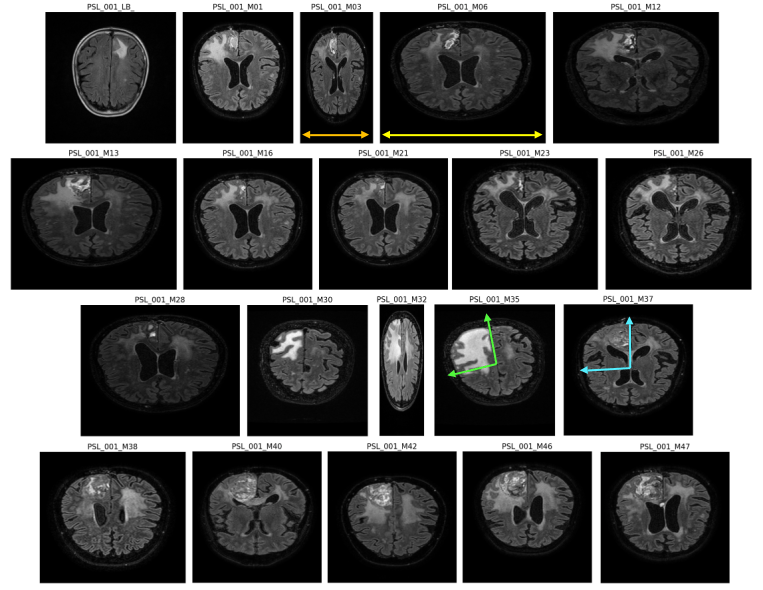

Data from :

segmented MRI

Data Nature

Rigid alignment

- Cancerous Growth (red - orange)

- White Matter Intensity reallocations (orange)

- Ventricule expansion (gray)

Registration difficulties